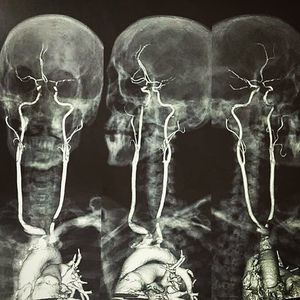

Masterpiece! Here is an contrasted MRI showing the origin, length & circulation of the carotid arteries!! By having a quick look, these are actually very diseased vessels. There's a lot of stenosis at the origin of the right brachiocephalic and left common carotid. There's also intermittent narrowing of the intracranial vessels, indicating atherosclerosis. The carotid artery begins at the aorta in the chest as the common carotid and courses up through the neck to the head. Place your hands on either side of your neck, and you can feel your pulse in your carotid arteries. Near the larynx, the common carotid divides into the external and internal carotid arteries. The external carotid arteries supply blood to the face and scalp. The internal carotid arteries supply blood to the brain. The most common location of atherosclerotic plaque buildup is the carotid bifurcation, where the common carotid divides into the internal and external carotid arteries. This specialized MR angiography is indicated to detect aneurysm, carotid stenosis/occlusion related to stroke, dissection (a tear in the artery wall that can cause stroke), or AVM's (arteriovenous malformations).